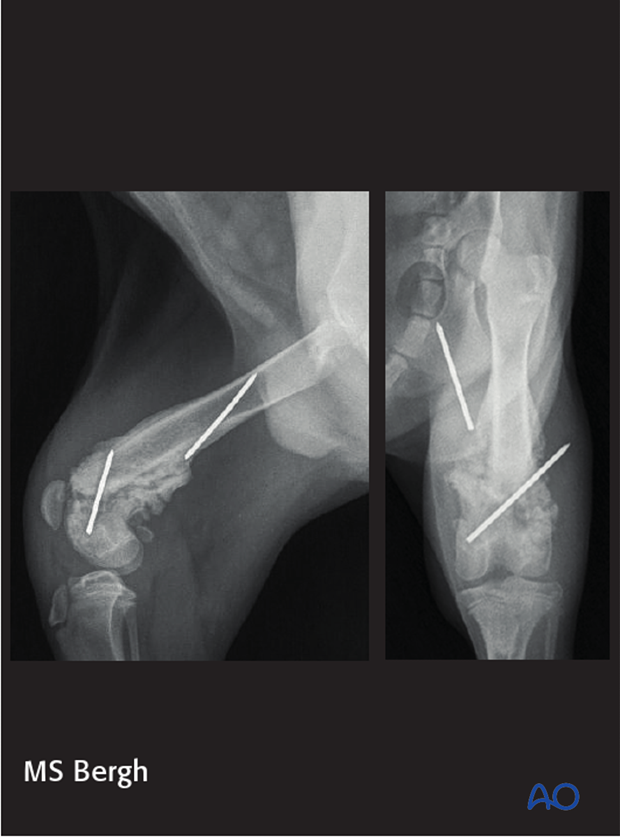

Images show implant loosening and migration. Following repair of a 33-A1 fracture with cross pins. Note loss of reduction of the fracture and significant healing occurring at the time of these radiographs. Despite implant failure, rotational and frontal plane alignment is good.